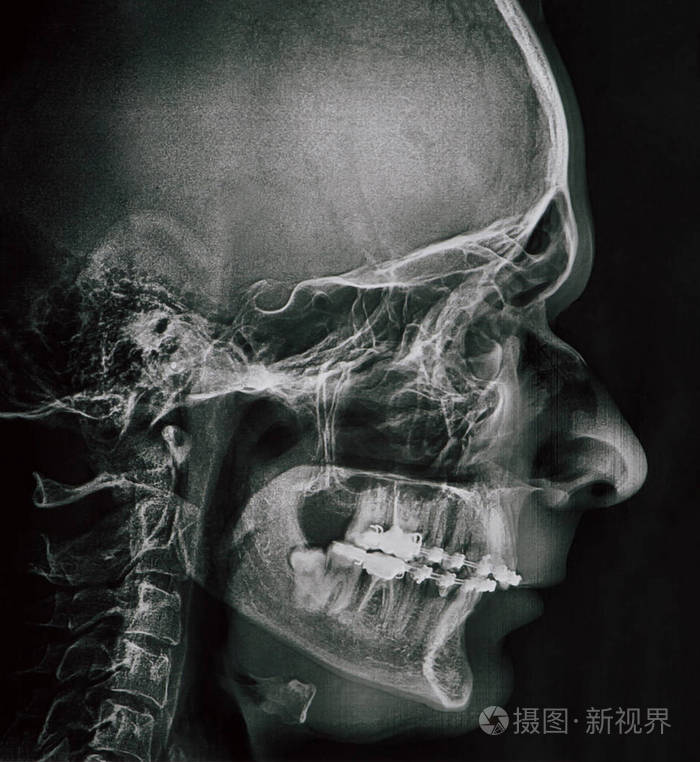

需要正颌吗?(内附侧面照及x光)

图片尺寸1080x1440

正畸医生主要通过头颅定位片来观察颅骨,颌骨的长,宽

图片尺寸2541x2001